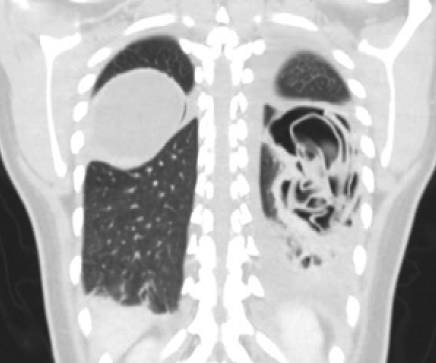

Guillermo Rencoret Palma, Marcelo Vivanco Lacalle, Felipe Andrés Castillo Henriquez, Giancarlo Schippacasse, Xabier De Aretxabala Urquiza, Victor Bianchi, Juan Hepp, Horacio Rios

|